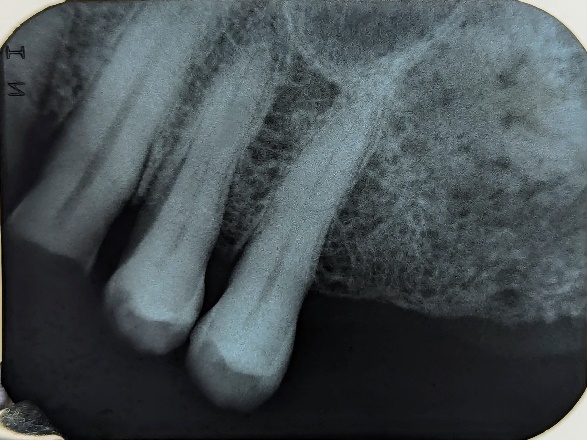

En la evaluación intraoral, se observó que el tejido blando del cuadrante uno presentaba una lesión de tipo inflamatoria de color grisácea-violácea vascularizada. Se realizaron radiografías periapicales de la zona en las cuales se observó un área mixta multiloculada, trabeculado óseo de forma irregular y con posible relación a la cortical del seno maxilar (Figura 1). Se solicitó Tomografía Computarizada de Haz Cónico (TCHC) y se realizó una biopsia incisional de la zona, abarcando un área de 1.5 x 1.5 cm.

Figura 1. Se observa (A) imagen clínica, radiografías periapicales de zona molares (B) y zona de premolares (C).